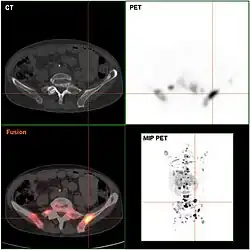

Endokrin aktive Tumoren (funktionelle NET) können frühzeitig aus den klinischen Symptomen vermutet und durch gezielte Laboruntersuchungen (etwa bei histologisch gesicherten NEN die Bestimmung von Chromogranin A im Serum[6]) des Blutes nachgewiesen werden. Inaktive Tumoren (nicht-funktionelle NET) werden oft erst spät durch ihre Größe oder infolge von Metastasen auffällig. Bildgebende Verfahren können die Lage des Tumors aufdecken: Sonographie, Computer- und Kernspintomographie, oder auch spezielle Szintigraphien wie die Somatostatin-Rezeptor-Szintigrafie mit Indium-111 oder MIBG-Szintigrafie. Neu entwickelt ist die Positronenemissionstomographie mit radioaktiv markiertem DOPA bzw. Edotreotid (DOTATOC), deren Sensitivität und Spezifität der klassischen Szintigraphie mit Somatostatinanaloga um bis zu 30 % überlegen ist.[7][8]